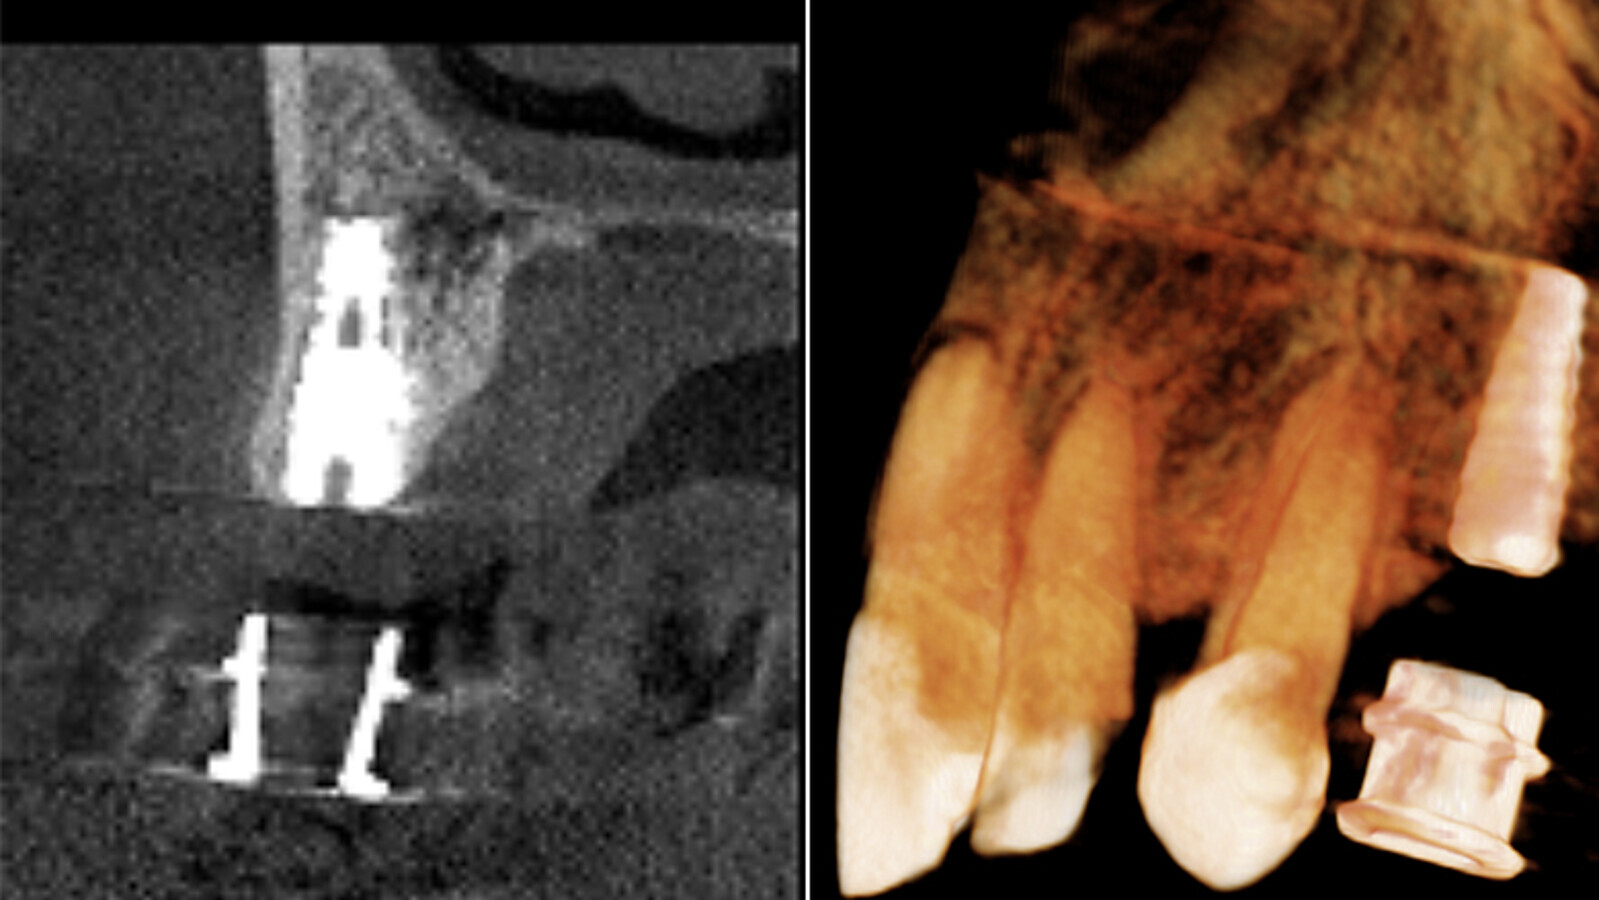

Figuras 6a, 6b. Tomografía Cone Beam post-quirúrgica.

Figuras 7a, 7b POST Qx. En la tomografía post-quirúrgica se evidencia el implante ya colocado en boca de igual forma a cómo se realizó en la planificación inicial, lo que confirma que esta técnica muy efectiva para el especialista, y que además minimiza riesgos.